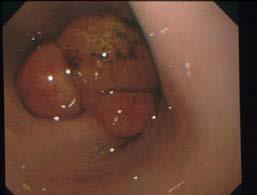

The cat was treated with Itraconazole 50mg SID and topically with Otoflush (Dermcare-Vet) and silver sulfadiazine ointment (Flamazine, Smith and Nephew). At recheck two weeks later, she had shown a 20% improvement with the skin remaining erythematous with some reduction in ulceration and minimal change in the subcutaneous nodules. She was changed to Fluconazole 50mg BID. At recheck another four weeks later, she had shown marked improvement as evident

in the image below (Figure 3). There were still multiple palpable nodular lesions in the subcutis but these had significantly reduced in size since the last visit (estimated 70% reduction) and there was one 8mm ulcer. Numerous Cryptococcus organisms were evident on FNA of a nodule and on a scraping of the ulcer. A liver profile biochemistry panel was normal with albumin 28.4g/L (RI 27-40). She was continued on Fluconazole 50mg BID with a plan to recheck in 8 weeks.